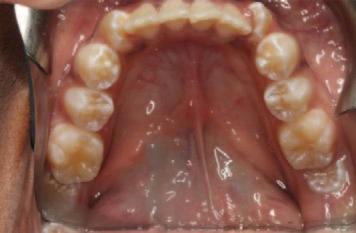

As with any form of clinical record, it would be highly beneficial for photographs of patients to be standardised and reproducible. This would allow for accurate monitoring of the dentition over time, forming a baseline pretreatment record (i.e., orthodontics, teeth whitening, aesthetic rehabilitations) as well as aiding comprehensive treatment planning.

Framing

Framing your subject (i.e., the smile, full arch or individual teeth) is vital to ensure the point of focus and purpose of the image being captured (Figures 1 and 2).

Full clinical photographic series

A full series of clinical photographs is extremely useful in the medicolegal documentation of a patient’s records. It certainly captures much more detail than any graphical electronic dental recording system. These photographs act as a record of the dental status of our patients, as well as the progression or stabilisation of disease over the duration of their care. It is also valuable to

be able to share these photographs with other dental professionals should a patient need to attend a new practice or clinic.

While there is no list of standard images required by any regulatory or indemnity body, the photographs shown in Figure 3 form a comprehensive set. The rationale for each view includes the following:

FIGURE 2: A systematic approach to taking clinical dental images is beneficial when starting out.

FIGURE 3: Example of a full clinical photographic series.